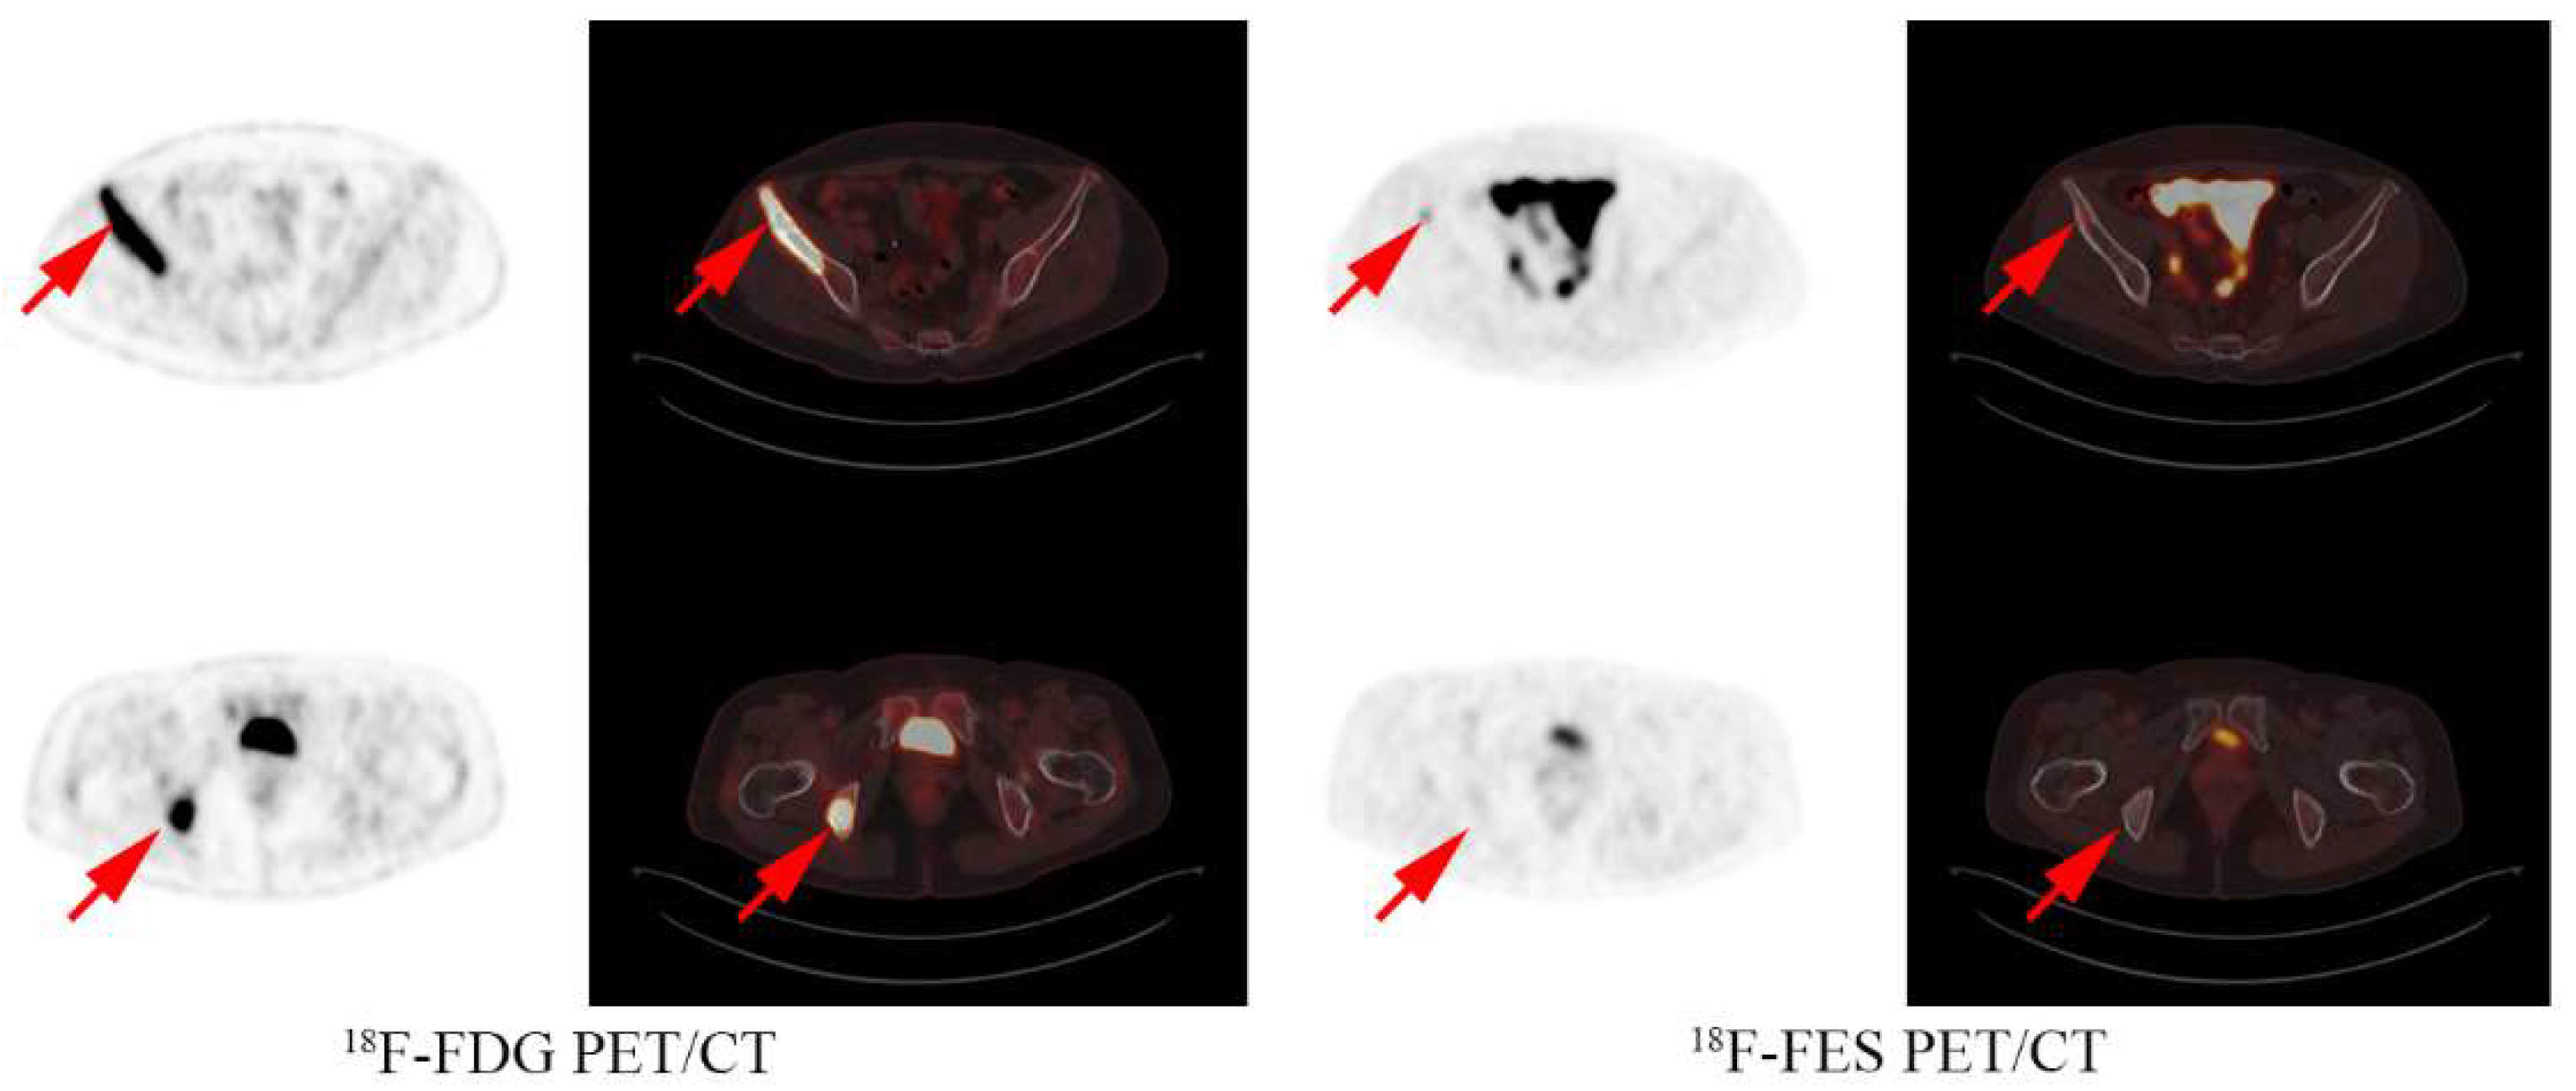

2.3. Image Interpretation

- Hao, W.; Li, Y.; Du, B.; Li, X. Heterogeneity of estrogen receptor based on 18F-FES PET imaging in breast cancer patients. Clin. Transl. Imaging 2021, 9, 599–607. [Google Scholar] [CrossRef]

- Yang, Z.; Sun, Y.; Zhang, Y.; Xue, J.; Wang, M.; Shi, W.; Zhu, B.; Hu, S.; Yao, Z.; Pan, H.; et al. Can fluorine-18 fluoroestradiol positron emission tomography-computed tomography demonstrate the heterogeneity of breast cancer in vivo? Clin. Breast Cancer 2013, 13, 359–363. [Google Scholar] [CrossRef]